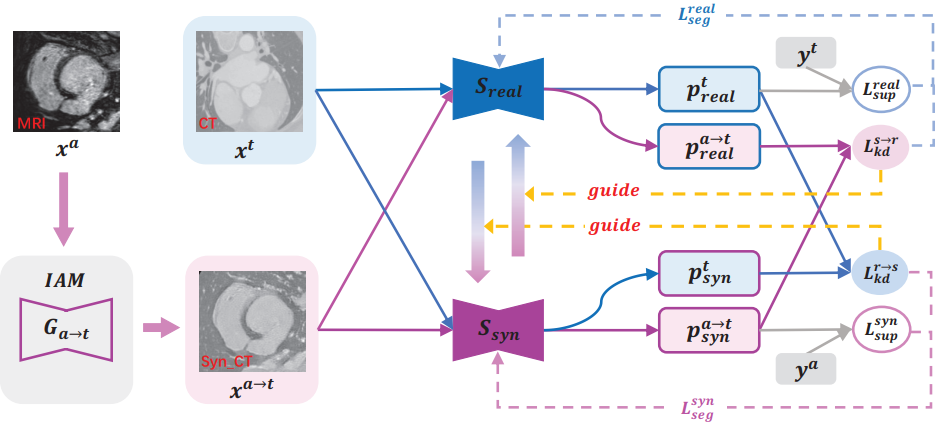

본 논문에서는 target 모달인 CT에 대한 segmentation 성능을 향상시키기 위해 source(보조) 모달인 MRI를 활용하게 됩니다. 이를 위해 mutual 기반의 Distillation 전략인 MKD(Mutual Knowledge Distillation) 이라고 하는 학습 기법을 설계하게 됩니다. 이에 대해선 Method 의 그림과 함께 설명 드리도록 하겠습니다.

IAM(Image Alignment Module)

본 논문에서는 Mutual Knowledge Distillation 프레임워크 설계에 있어서 IAM 이라고 하는 추가적인 모듈을 설계하게 됩니다. 위 그림의 좌측에 해당하는데요, 이는 GAN 의 Generator를 통해 Synthetic CT 이미지를 생성하는 모듈입니다.

target 모달인 CT 이미지는 그대로 두고, 보조 모달인 MRI 이미지를 합성 CT 이미지로 만들어 내는 것입니다. Discriminator를 활용해서 최대한 CT 영상 틱한 합성 영상을 만들어 내는 것이지요.

하지만 본 논문에서 사용한 데이터셋은 unpair한 상황이기 때문에 각 모달의 예측을 mutual learning에 사용하지는 못하게 됩니다. 그래서 본 논문에서는 GAN을 통해 MRI 영상을 CT 스타일의 영상(x^{a->t})으로 합성하고 real CT 영상(x^t)과 함께 학습에 활용하였습니다.

MKD(Mutual Knowledge Distillation)

그림에서 보시다시피 segmenation 모델은 S_{real}과 S_{syn}으로 구성되어 있고 두 영상 x^{a->t}와 x^t는 어쨋든 모두 CT 스타일의 영상이기 때문에 동일한 모델에 통과시켜도 무방합니다. 도메인이 동일하기 때문이죠.

우선 S_{real}과 S_{syn} 는 각각 x^t와 x^{a->t}로부터 직접적인 학습이 일어나게 됩니다. 한마디로 gt를 통해 학습이 일어난다는 뜻이고, 위 그림에선 L_{sup}가 이에 해당합니다. 그리고 계산 식은 아래와 같습니다. Cross Entropy loss와 dice loss의 결합으로 이루어 져 있습니다.

또한 이런 직접적인 학습 뿐만 아니라 반대쪽 segmentation 모델의 예측을 사용해서 간접적인, mutual한 학습을 하게 됩니다. 위 그림에선 L_{kd}가 이에 해당하게 됩니다.

그리고 위의 직접 학습과 간접 학습을 결합하여 S_{real}과 S_{syn}를 학습시키는 LOSS는 아래 식과 같습니다.

1. unpair하다는 뜻은 말씀하신 거 처럼 domain의 unpair가 아닌 서로 다른 곳을 보고있는, align 자체가 맞지 않는 쌍의 MRI-CT 이미지를 뜻합니다. 그럼에도 GAN을 통해 합성 CT 영상을 생성하여 real CT 영상과의 학습이 가능한 이유는 real CT와 Synthetic CT 사이에 특별히 직접적인 전이가 이루어지지 않기 때문입니다. real CT와 Synthetic CT는 unpair한 상황이기에 각각의 gt가 존재합니다. 그리고 각 모델 (S_real, S_syn)은 자신의 gt를 통해 supervised 방식으로 학습되게 됩니다. 여기에 추가적으로 kd 방식이 적용되게 되는데 이는 모델의 화살표 색깔을 보시면 이해하기 수월합니다. 파랑색 화살표 기준으로 real CT 이미지는 S_real과 S_syn에 통과되어 예측을 수행하게 되고 이 둘 사이에 KD loss가 계산되게 됩니다. 반대의 경우도 마찬가지입니다. 정리하자면 unpair한 real CT와 Synthetic CT 사이의 직접적인 distillation 과정은 없는 것입니다.